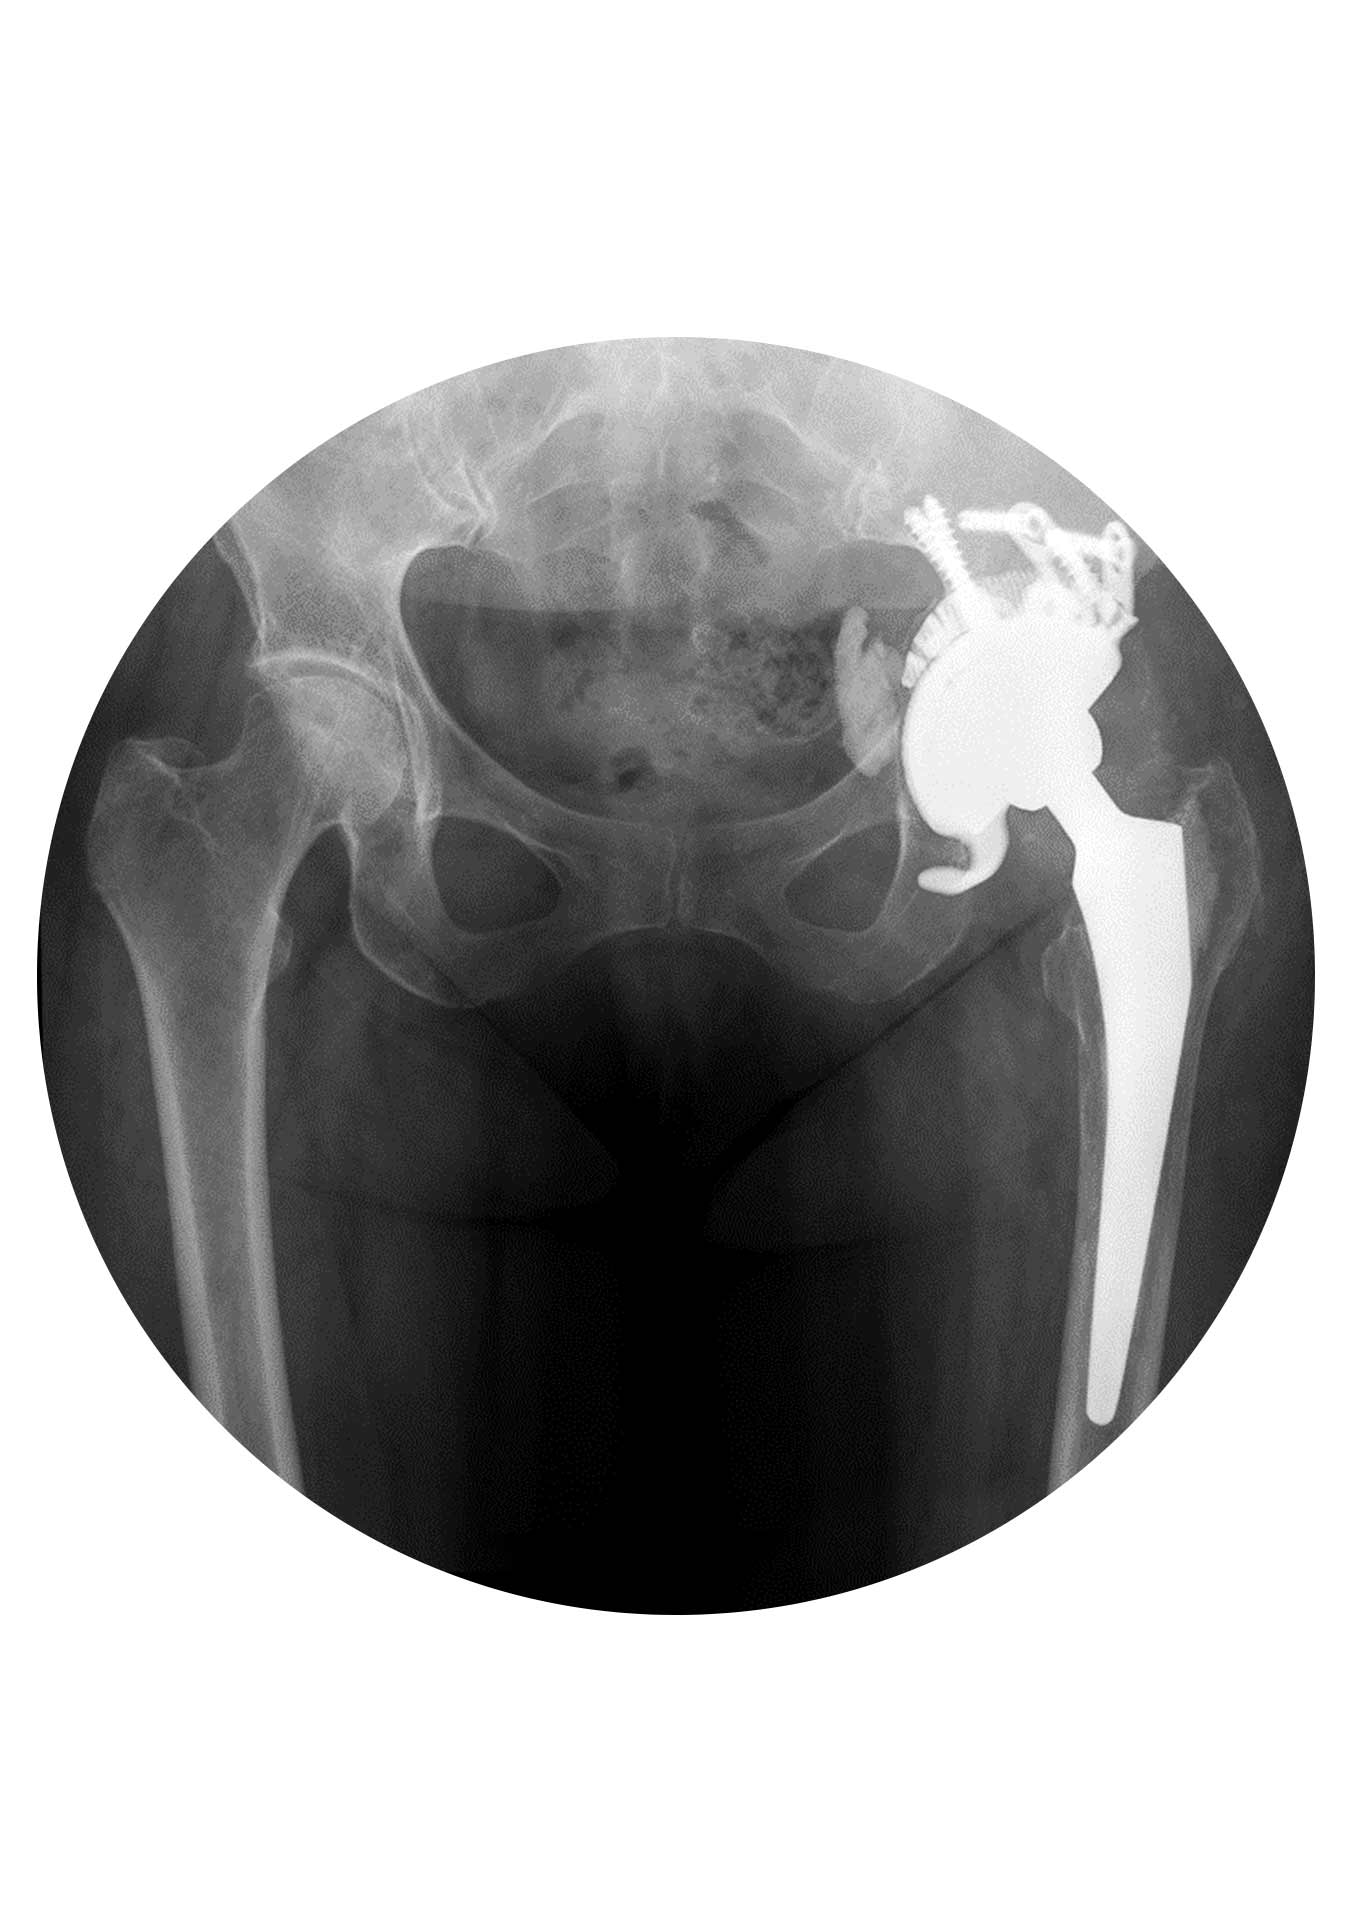

O objetivo dessa cirurgia é corrigir o problema para que a anca volte a funcionar normalmente outra vez. O principal obstáculo e desafio destas cirurgias é a “falta de osso”, ou seja, a destruição óssea quer pela causa da falência quer pela remoção dos implantes no momento da revisão. A sua complexidade varia muito dependendo da causa da falência e pode ir desde a simples substituição de um “plástico gasto” (polietileno) até à remoção total da prótese e substituição por outra (no mesmo tempo cirúrgico ou algumas semanas após) no caso de uma infeção.

Primeiro: remoção do implante(s) deficiente(s) e preservação dos implantes competentes. Este é muitas vezes o momento mais complexo da cirurgia de revisão. O seu objetivo principal é remover apenas os implantes que precisam de ser substituídos e neste processo causar a menor lesão possível na estrutura óssea da articulação para facilitar a fase seguinte.

Segundo: reconstrução da “nova” articulação. Embora o momento da remoção dos implantes seja importante no resultado da cirurgia de revisão, esta é na sua essência uma cirurgia de reconstrução.